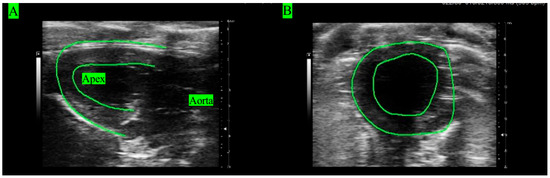

2.2. Echocardiography Images (ECHO)

3.1. ECHO Analyses